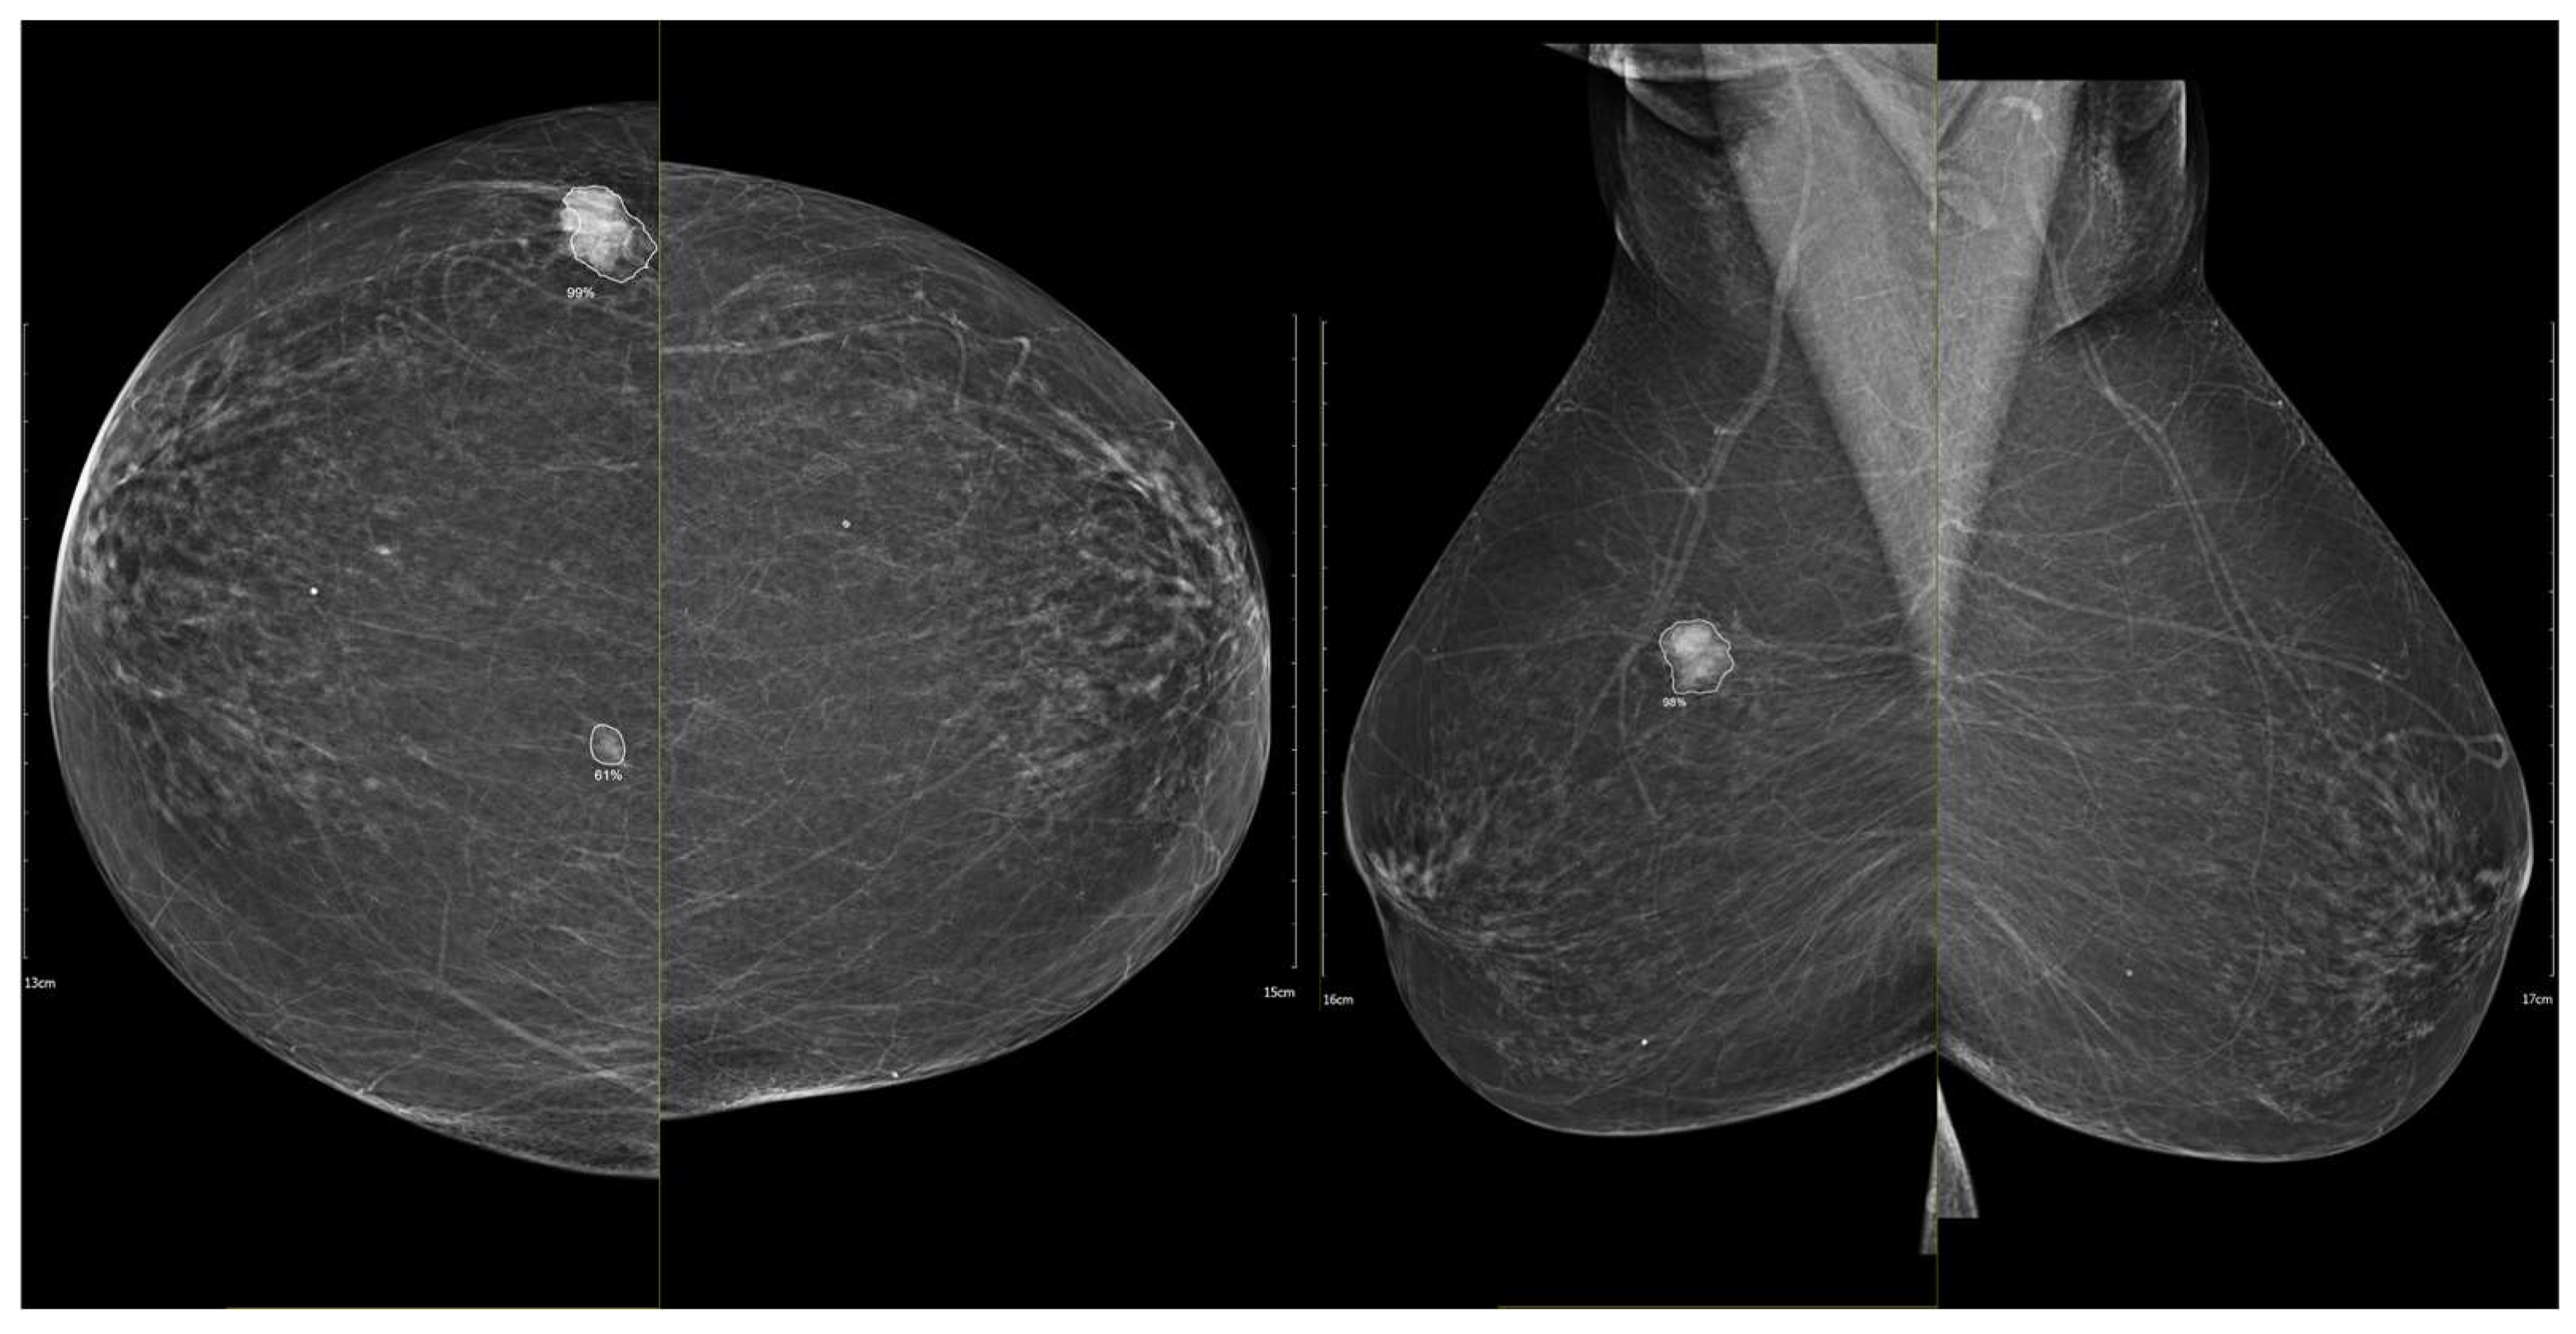

To illustrate the behavior of the iCAD ProFound AI® system across different biological phenotypes, Figure 9 and Figure 10 present representative examples corresponding to Group 1 (luminal) and Group 2 (HER2-positive/triple-negative) tumors. In both cases, the algorithm correctly identified the lesion with high confidence and localized regions corresponding to malignant radiomic traits. These findings should be interpreted in the context of case-level AI assessment rather than lesion-specific prediction.

Figure 9. Example of iCAD ProFound AI® output for a luminal A carcinoma. The lesion detected on the low-energy image is automatically outlined by the AI system with an assigned malignancy probability. The outline shows the regions of highest AI attention, corresponding to irregular shape and spiculated margins, typical of luminal tumors.

Figure 10. Example of iCAD ProFound AI® output for a triple-negative breast carcinoma. The lesion detected on the low-energy image is automatically outlined by the AI system with an assigned malignancy probability. The outline shows the regions of highest AI attention, corresponding to oval shape and microlobulated, noncircumscribed margins.